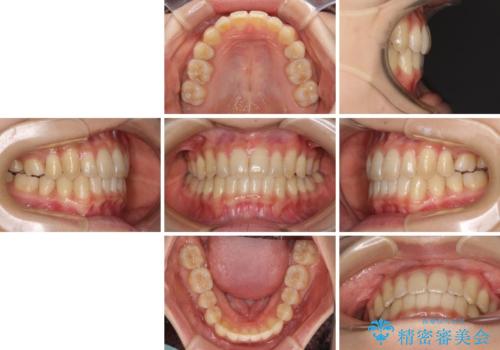

反対咬合が改善され、食いしばり癖もなくなり、顎関節の負担が軽減されました。

上顎骨を拡大したことで前歯に隙間ができ、1ヶ月ほど恥ずかしい時期がありましたが、しっかりとした咬み合わせに仕上がり、患者様には大変満足していただきました。